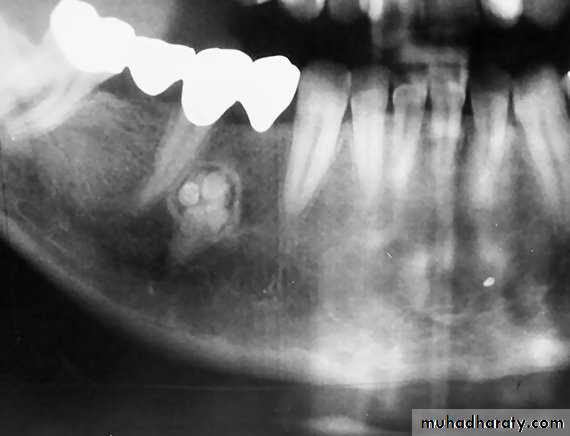

Raioraghical examination may demonstrate unlocular or multilocular types. Unilocular ameloblastomas may be confused with benign cysts. The tumors frequently absorbs the alveolus surrounding ,the roots of teeth and may absorb root ends.

Ameloblastoma grow by extension into adjacent tissues and may perforate the investing bone. A biopsy should precede treatment since

these tumors frequently present with individual characteristics.